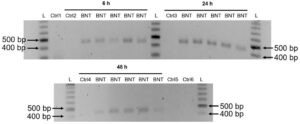

14. The Pfizer vaccine mRNA gets copied (“reverse-transcribed”) into DNA and inserted into the cellular genome

The official mRNA vaccine narrative maintains that the modified mRNA contained in the vaccine will not be replicated in vivo; expression of the spike protein should therefore cease once the injected RNA molecules have been degraded.

The limited experimental studies available [9,10] suggest that the injected modified mRNA should be degraded within days to a few weeks of the injection. This is obviously difficult to square with the observed long-lasting expression; in some form or other, the genetic information appears to be perpetuated in vivo.

A recent experimental study from Sweden [11] has shown that human-derived cells can copy the Pfizer mRNA vaccine into DNA and then insert it into their own chromosomal DNA. The image shows the key evidence from this study. The cells were exposed to the vaccine for the lengths of time indicated. Cellular DNA was then isolated, and inserted DNA copies of the vaccine mRNA detected by PCR amplification of a fragment 444 base pairs (bp) in length.

All samples labelled with “BNT” had been treated with the vaccine, and they all show a PCR product of the expected length, as is evident from comparison to a DNA fragment length standard (“L”). Samples labelled with “Ctrl n” were controls: Ctrl 1– 4 contained DNA from cells not incubated with vaccine, Ctrl 5 contained RNA (not DNA) from vaccine-treated cells; Ctrl 6 contained the same but was additionally treated with RNAse, which step was also performed in the purification of DNA samples. As expected, none of the control samples contain the PCR product.

Considering Aldén’s observation of DNA insertion in every single experimental sample, it seems highly likely that this will also occur in vivo. Beyond providing a plausible mechanism for perpetuating the expression of spike protein, DNA insertion also poses risks of genetic damage, leading to cancers and leukemias.